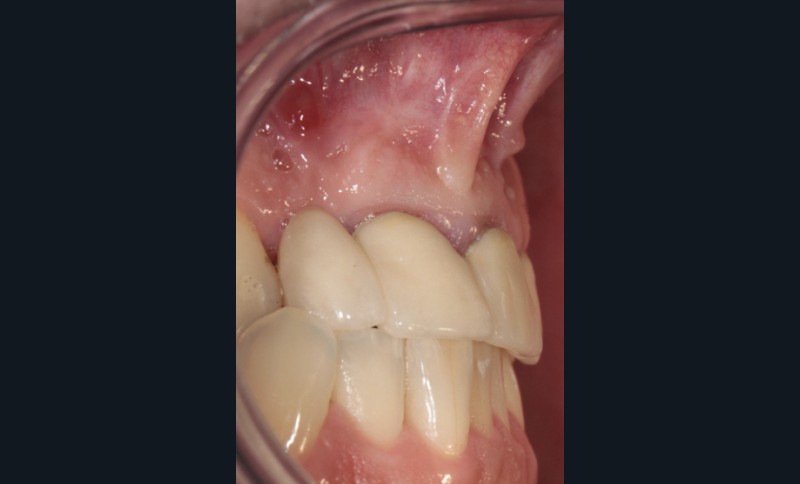

L’examen endobuccal montre deux fistules en regard des apex de 12 et 21 (fig. 1). Nous notons la présence d’une classe III squelettique, d’une occlusion inversée du côté droit (fig. 2) et des édentements non compensés au niveau de 26 et 36. L’orthopantomogramme révèle la présence d’une volumineuse lésion kystique qui s’étend de la 12 à la 22 (fig. 3).